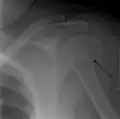

Multi-fragmented, or comminuted fracture of the proximal humerus with involvement of the greater tuberosity

Proximal humerus fracture